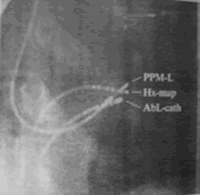

要实现希氏束起搏,首先要经股静脉放置一根标测电极,以记录到希氏束电图作为标志,然后,操作螺旋电极靠近希氏束,试起搏夺获希氏束后,将螺旋电极旋进组织中 ......